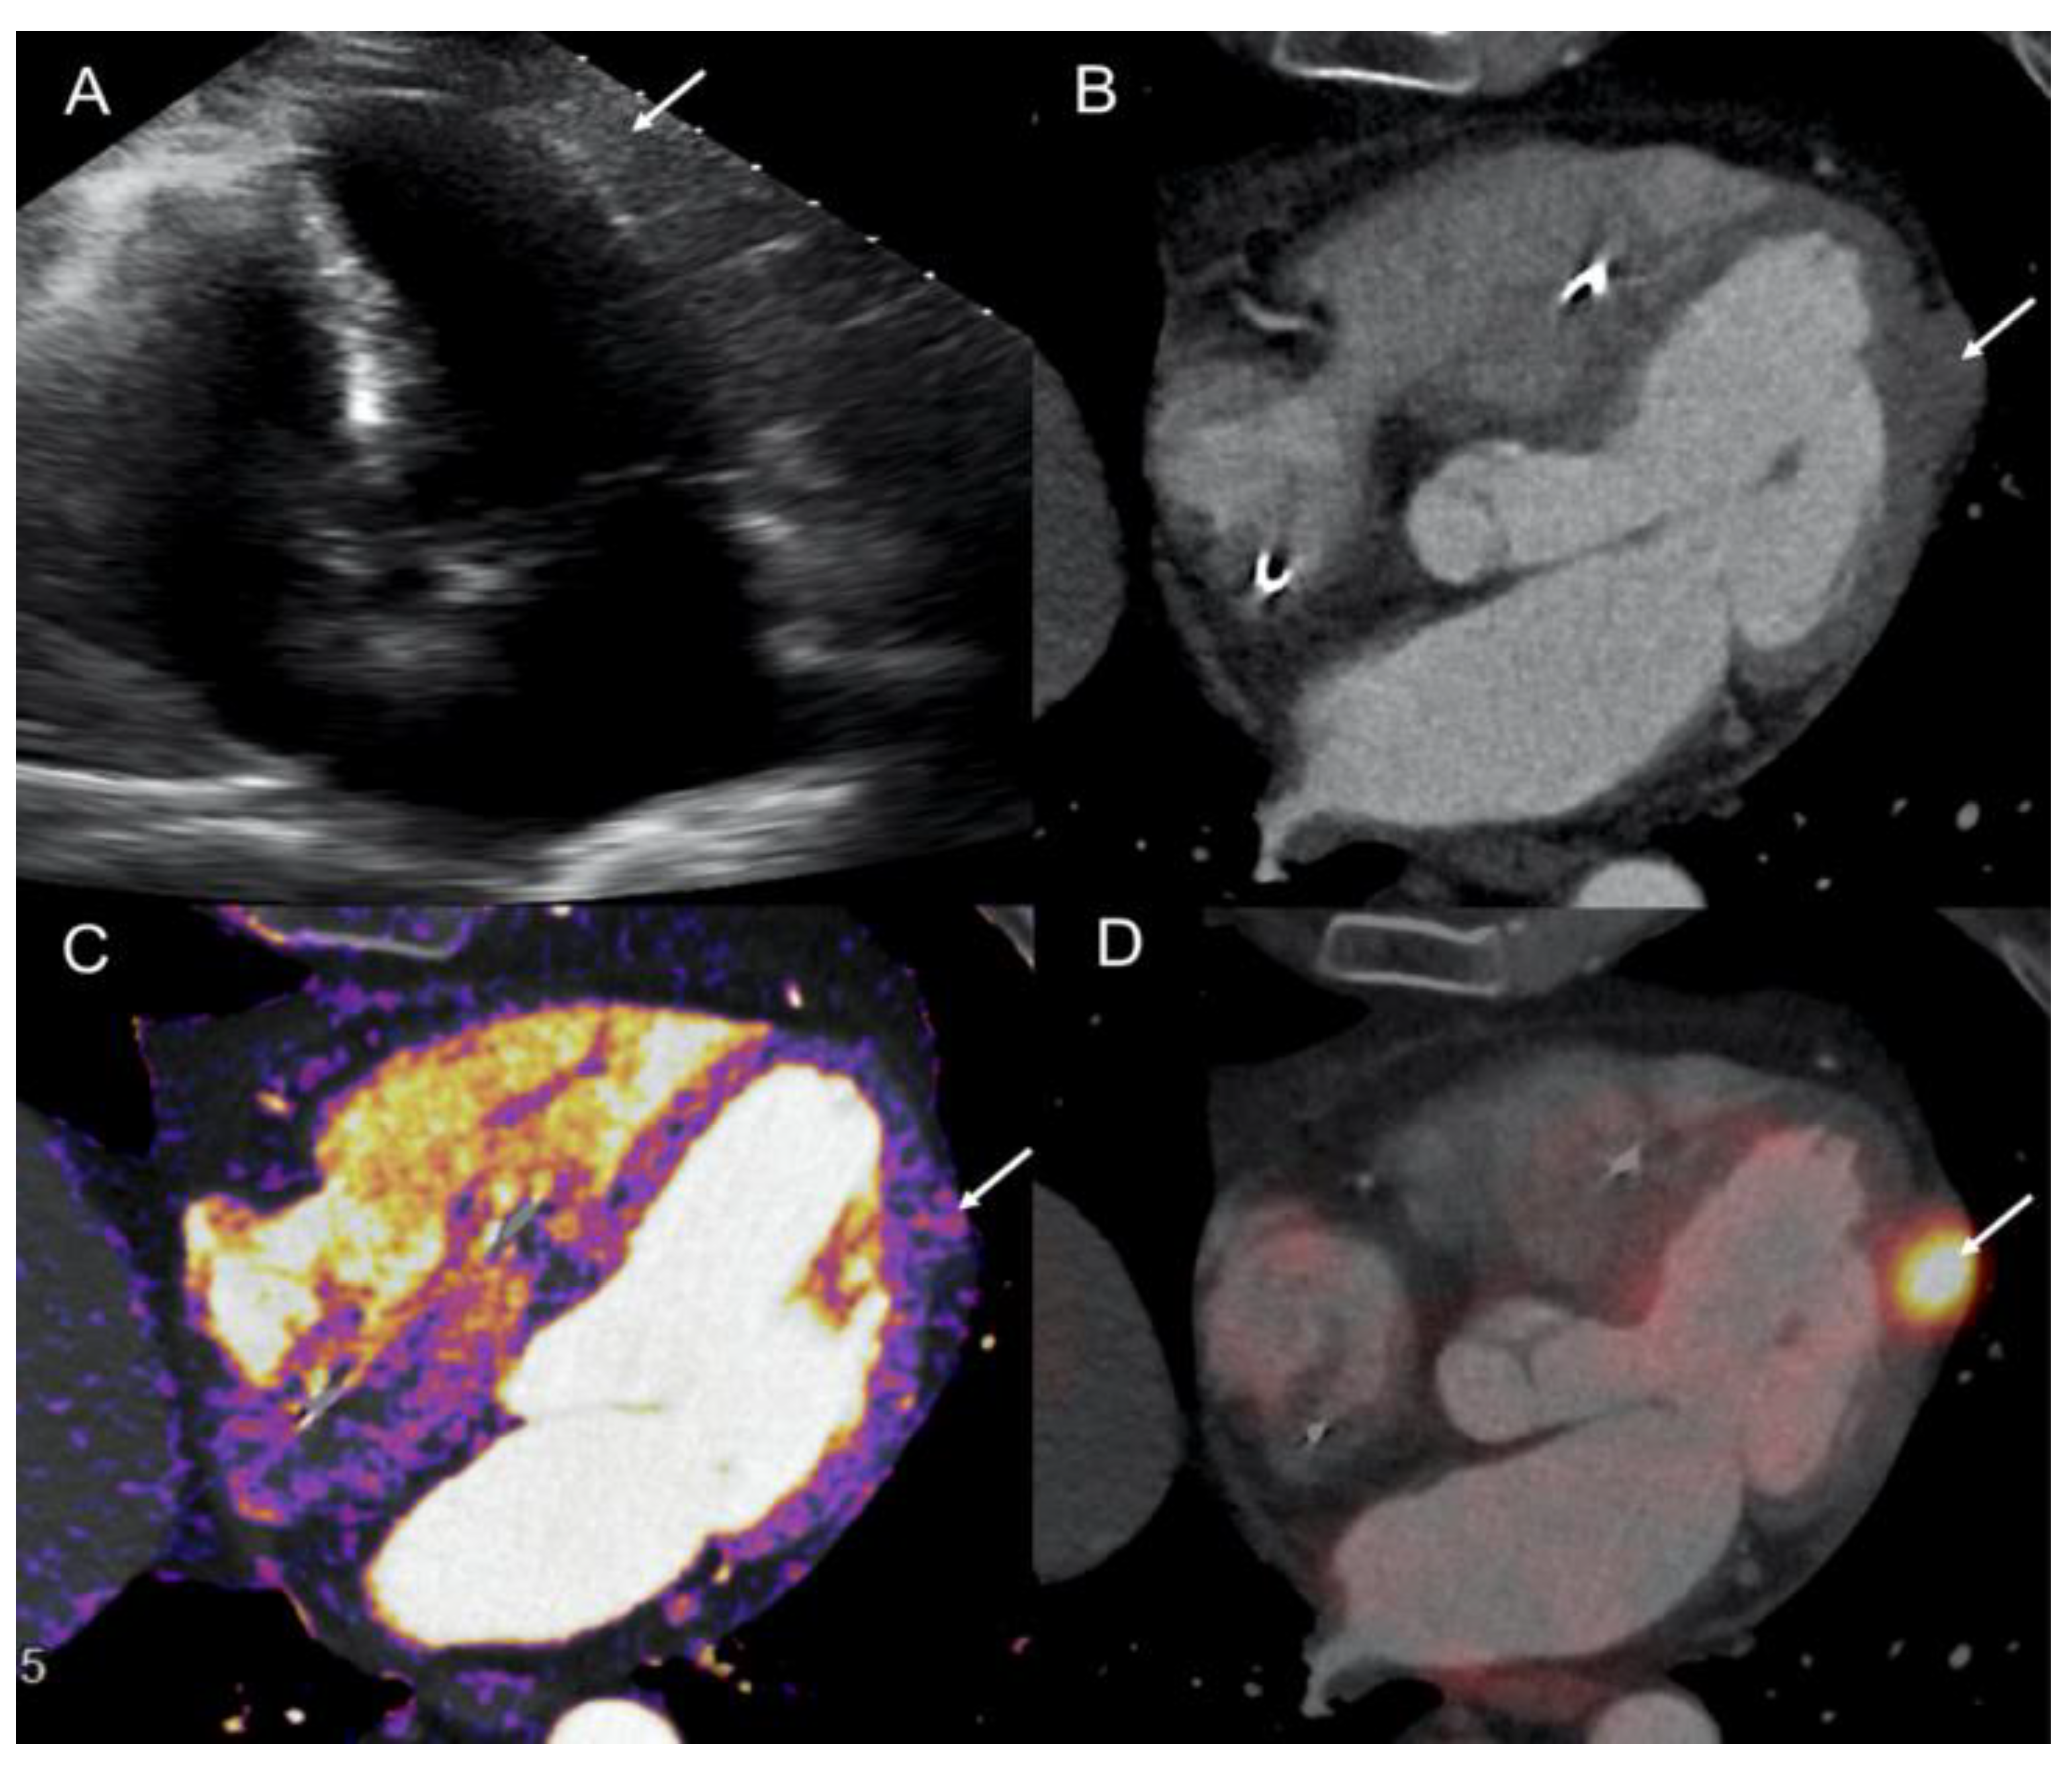

2.2. Patient 2

- CMR and Cardiac-CT enable high-resolution, multiplanar imaging crucial for accurate anatomic localization, mass mobility assessment, and tissue characterization for noninvasive diagnosis confirmation;

- TTE remains clinically useful for cardiac function evaluation and tricuspid valve insufficiency detection (carcinoid heart disease), particularly in patients with functioning si-NETs and carcinoid syndrome;